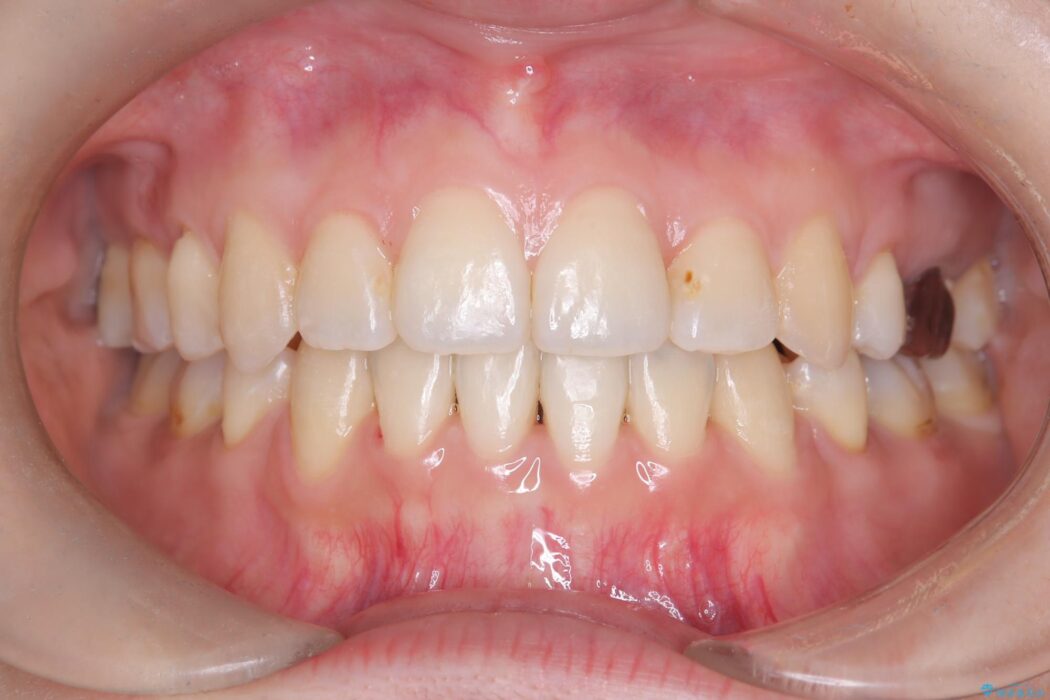

口元を下げて前突感を無くしたい、下の歯の凹凸も無くしたいとご来院された患者様です。

アゴの骨格的なズレがあったため、歯の真ん中を完全に合わせることは不可能と説明。上下4本抜歯を行い、ワイヤー矯正で噛み合わせの大きな改善を目指しました。

口元の突出感が改善され、大変ご満足いただけました。